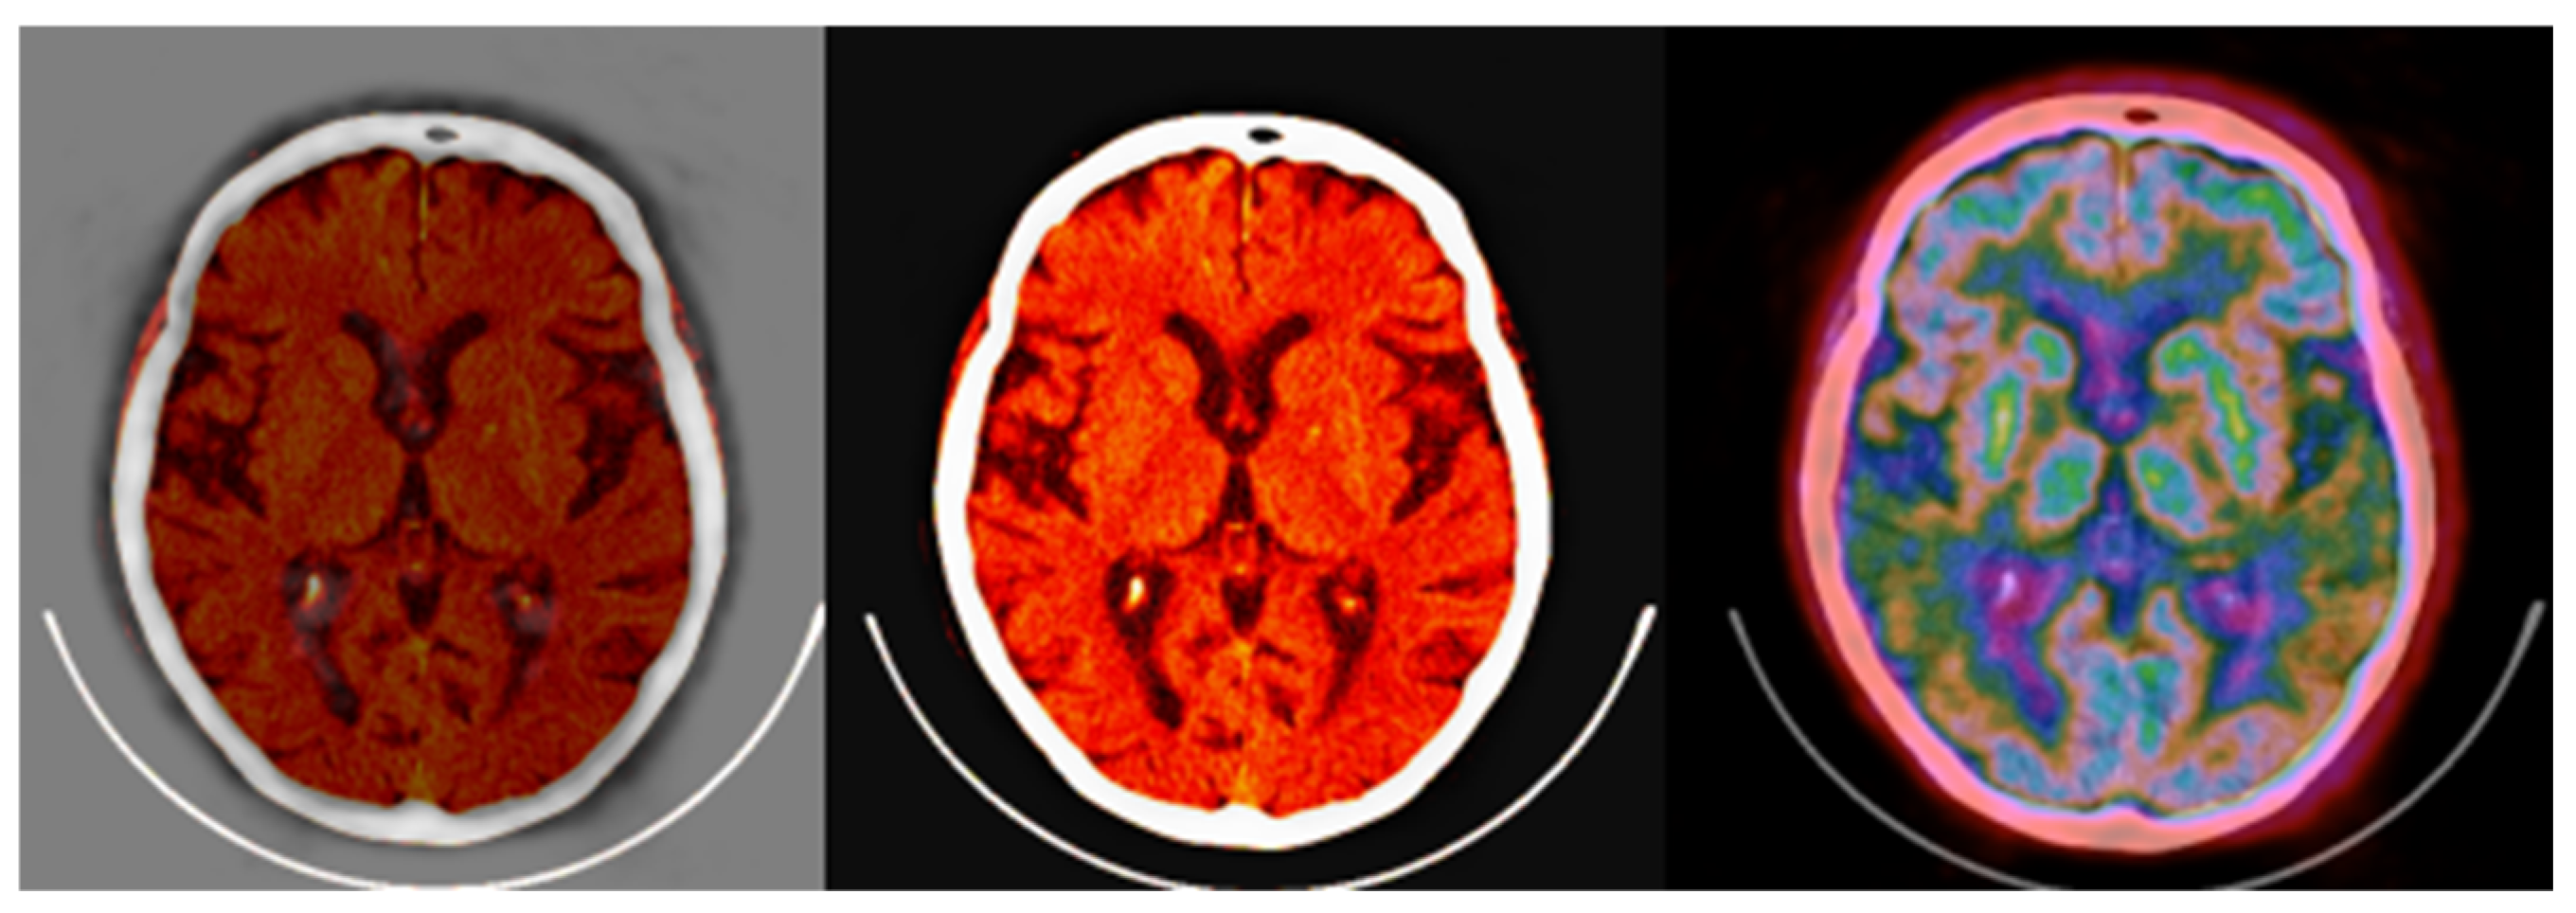

Color as a High-Value Quantitative Tool for PET/CT Imaging

2. Materials and Methods

3.1. CIT Application

3.2. Colormap Folding Application